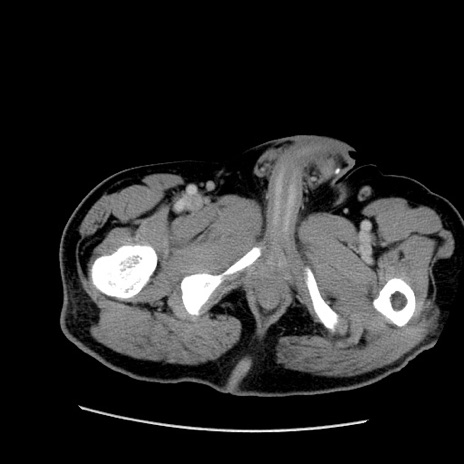

症例22(横断像)

【症例】50歳代男性

【主訴】腹痛

【現病歴】AVMからの被殻出血のため回復期リハ病棟入院中。 本日午後3時頃急に下腹部痛が出現した。

【既往歴】AVM、被殻出血、虫垂炎、高血圧

【身体所見】意識晴明、左半身不全麻痺、会話の理解は良好、36.5°C、腹部:膨隆、全体に板状硬、下腹部正中に圧痛点あり、反跳痛-、筋性防御不明、右下腹部にope scar

【データ】WBC 9400、CRP 0.06